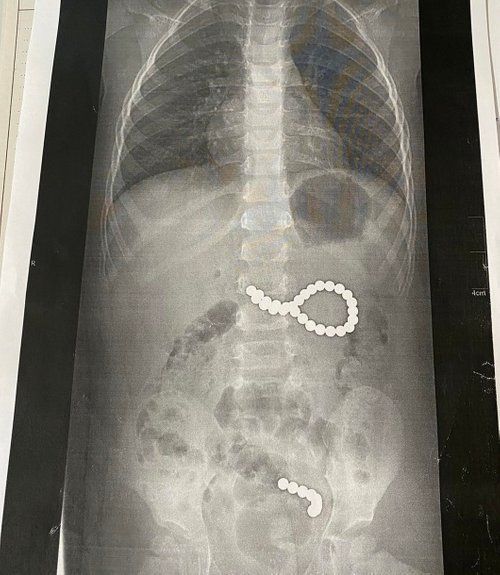

Дворічна дівчинка з Дрогобицького району проковтнула 36 магнітних кульок від конструктора. У суботу, 6 вересня, дитину госпіталізували до львівської обласної дитячої лікарні ОХМАТДИТ.

Дев’ять кульок під дією магнітного поля утворили ланцюжок і потрапили в кишківник, ще 27 кульок утворили неправильне коло і потрапити в кишківник не могли. Дівчинку довелося терміново оперувати, пише ZAXID.NET.

Перші дев’ять магнітних кульок дитина проковтнула у п’ятницю, 4 вересня. У суботу дівчинка проковтнула ще 27 магнітних кульок і лише тоді про це зізналася батькам.

"Дев’ять кульок, які дитина проковтнула у п’ятницю, утворили ланцюжок, бо було сильне магнітне поле. І вони пройшли зі шлунка в тонкий кишківник. А ті 27 магнітних кульок, які дитина проковтнула у суботу, утворили неправильне коло і їх терміново треба було діставати. Кульки були діаметром 4 мм, найвірогідніше, з якогось конструктора", – розповіла виданню хірургиня ОХМАТДИТу Оксана Горбач.